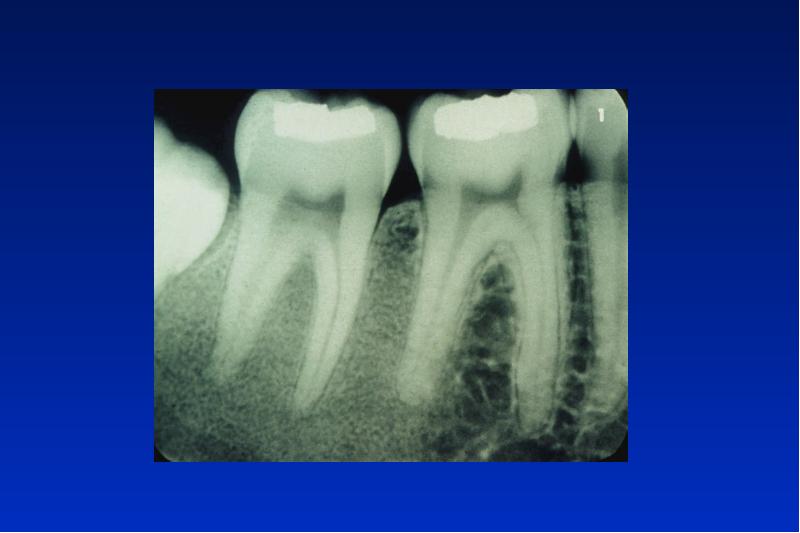

- 21. Odontogene Keratozyste Lok: UK Alter: 20 - 30, 50 - 60